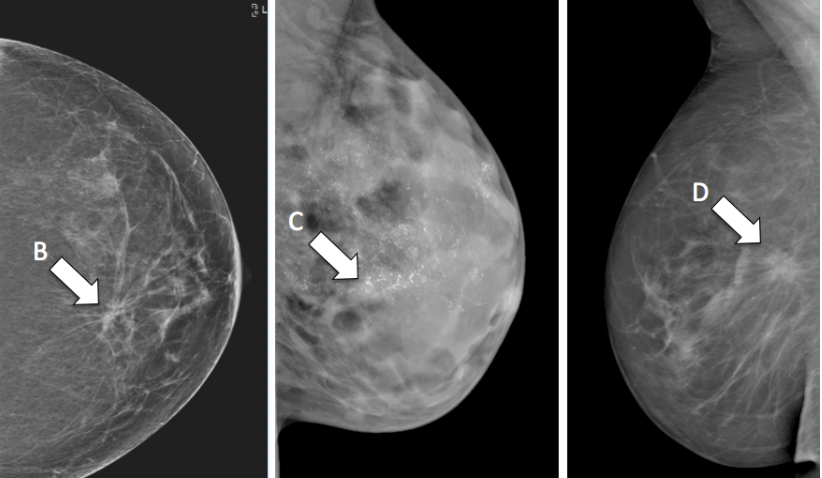

asymmetry

B - architectural distortion

C - microcalcification

D - mass